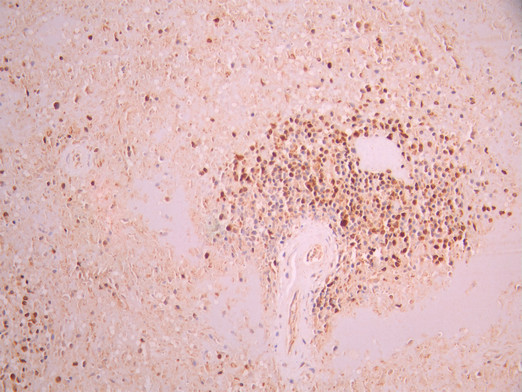

IHC image of CSB-RA775975A0HU diluted at 1:100 and staining in paraffin-embedded human spleen tissue performed on a Leica BondTM system. After dewaxing and hydration, antigen retrieval was mediated by high pressure in a citrate buffer (pH 6.0). Section was blocked with 10% normal goat serum 30min at RT. Then primary antibody (1% BSA) was incubated at 4°C overnight. The primary is detected by a Goat anti-rabbit polymer IgG labeled by HRP and visualized using 0.05% DAB.